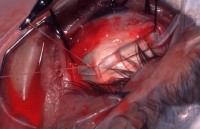

1.peritomy

eye speculum 으로 벌린 후 tooth + wescott's scs로 cunjuctive 를 분리

2.Insertion of squint hook under rectus muscle , insertion of bridel suture

cornea cover 올려 놓은 후

3-0black silk + SB Kit 내의 muscle hook(가장 큰것) 으로 걸고 tagging suture -

->교수님께서 기본 set내의 scs로 cut 하고 mosq tagging은 안하고 실의 끝부분을 묶어 놓음

->needle의 끝부분에 물어서 뒤로 back 으로 suture 함(needle 뾰족한 부분을 holding)

4군데 rectus muscle을 tagging suture 다함

Assist는 주걱모양의 Retractor

3.indirect lens 로 망막 열공된 부위 확인

while viewing with indirect opthalmoscope check position of indentation in relation to break

20D indrect lens 를 보면서 열공된 부분을 marker로 표시

->교수님 7glove를 낀 후 head lamp 쓰심, circulating nurse는 glove out을 하고

->방에 불 off

얇은 marker 표시 전에 면봉으로 닦아 내신다.

망막 set 내에 있는 depressor

SB Set내에 있는 가장 작은 hook으로 확인